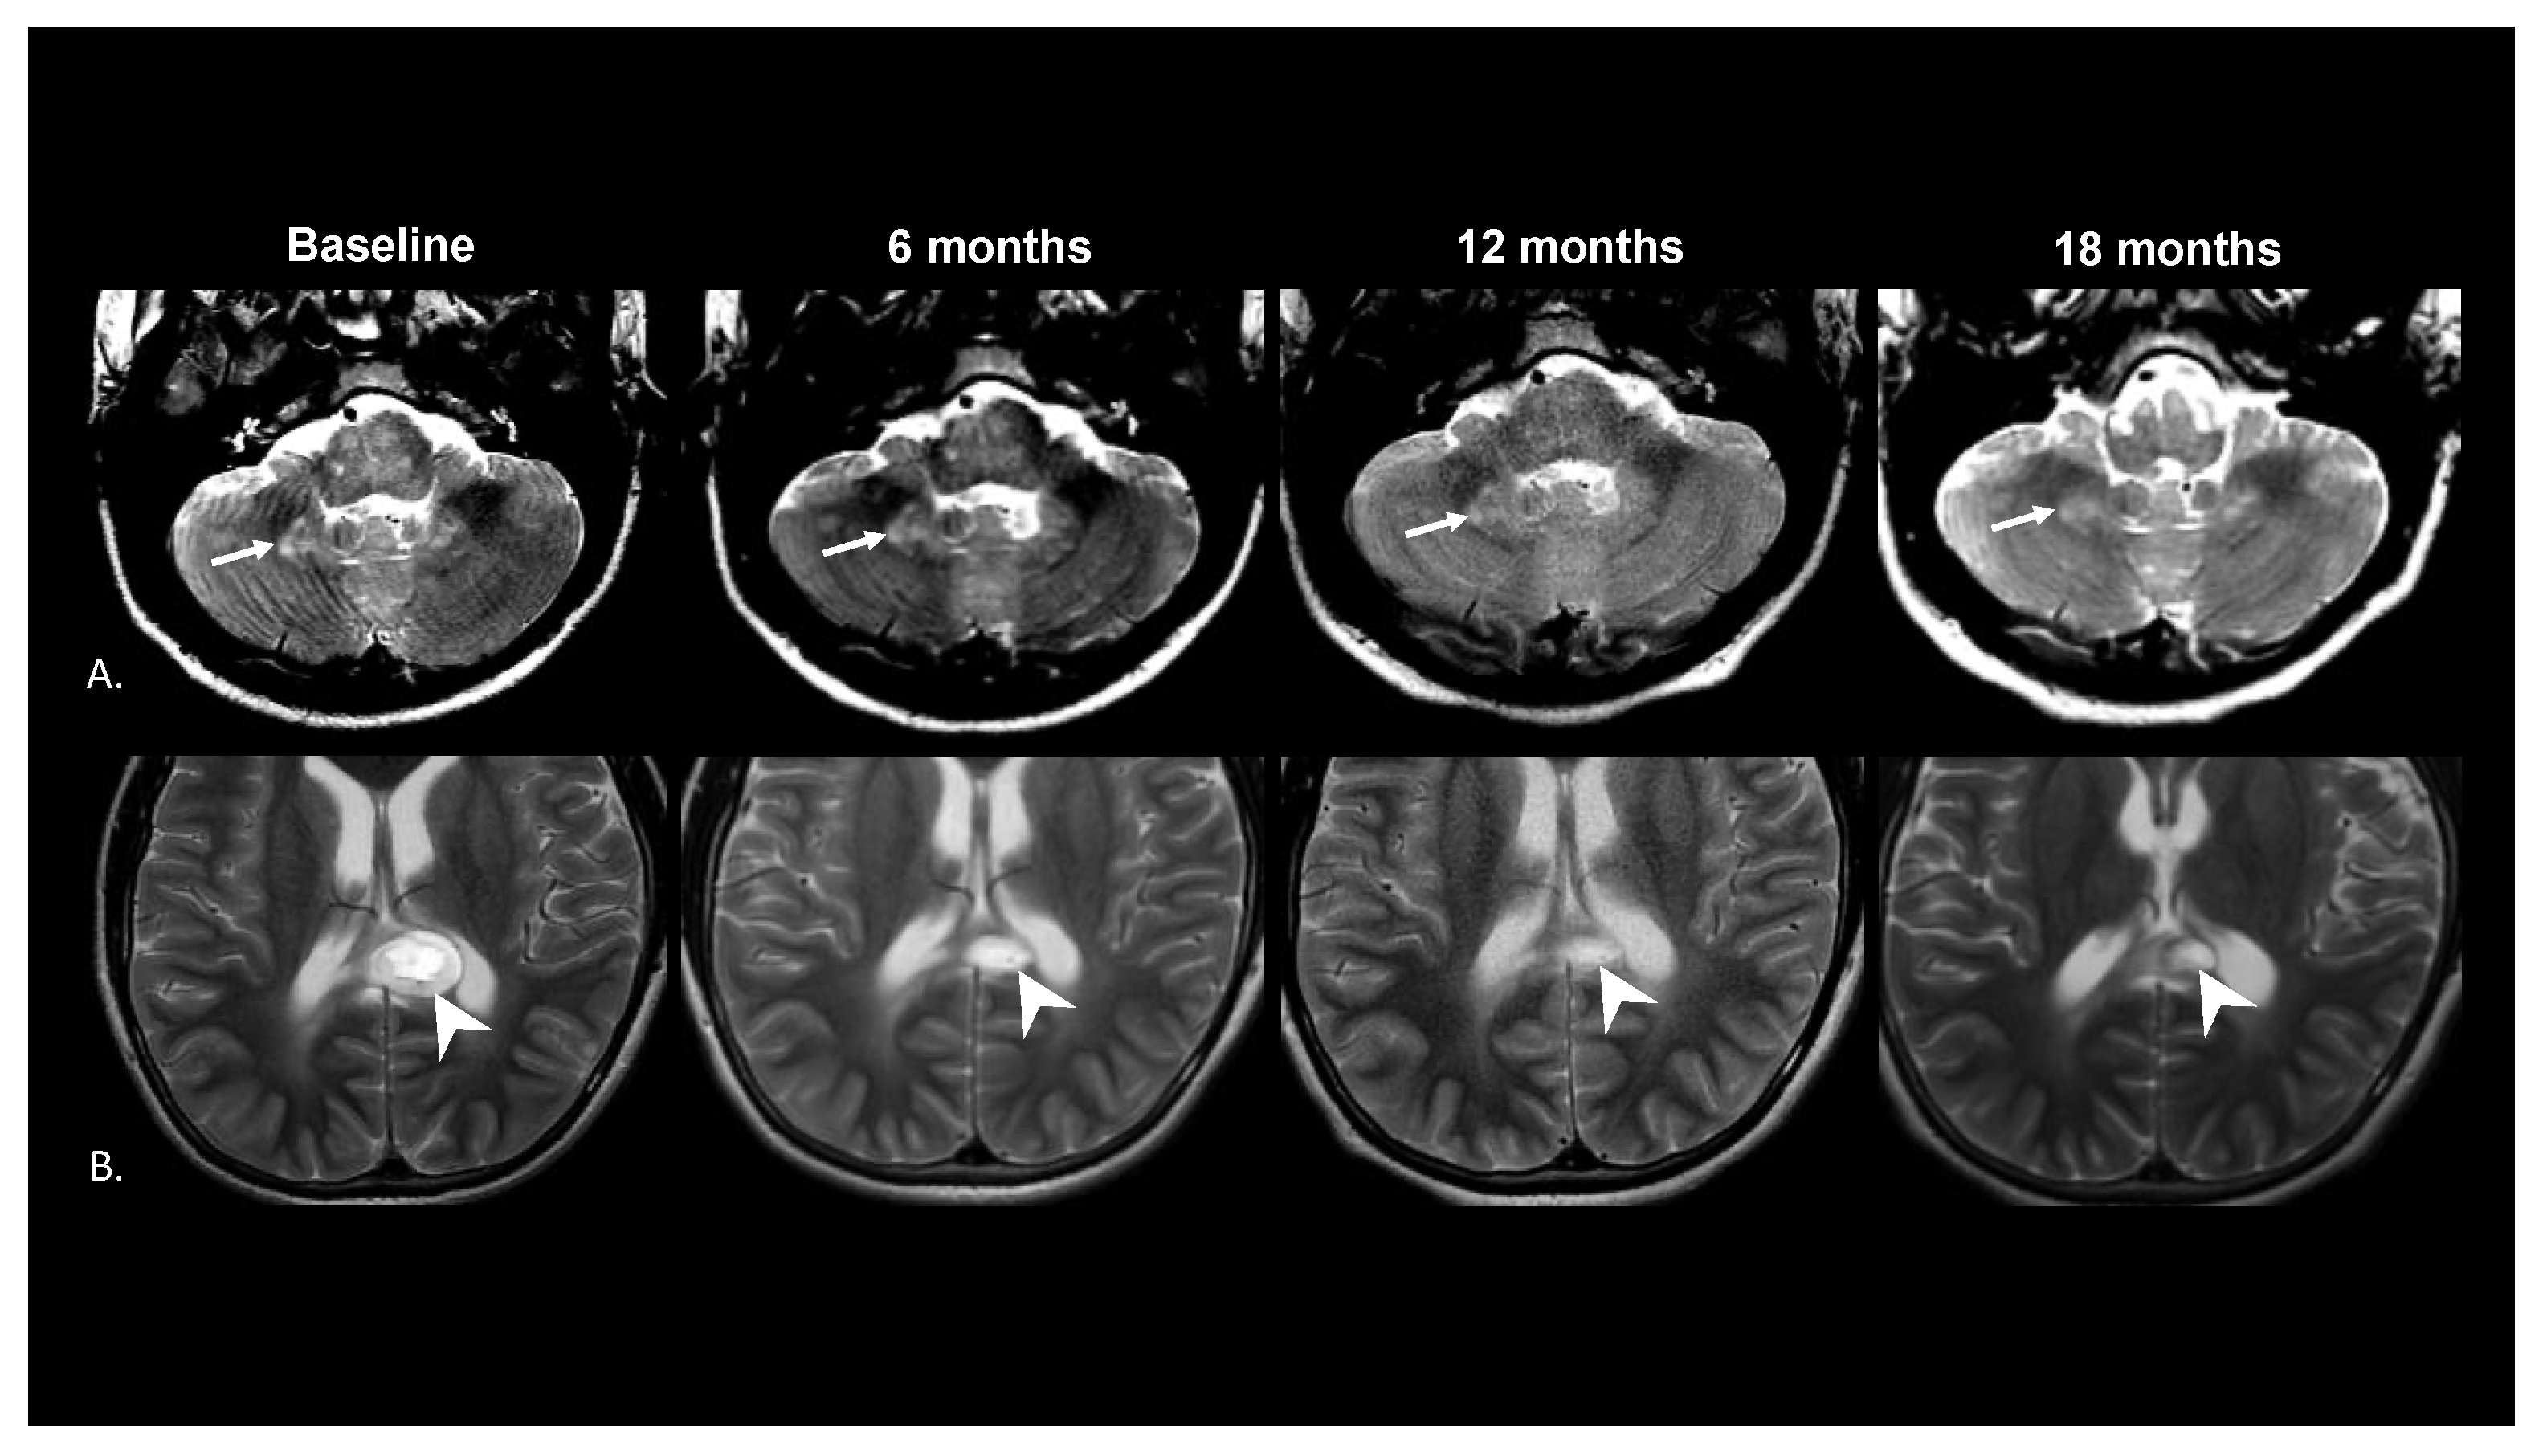

3. Results